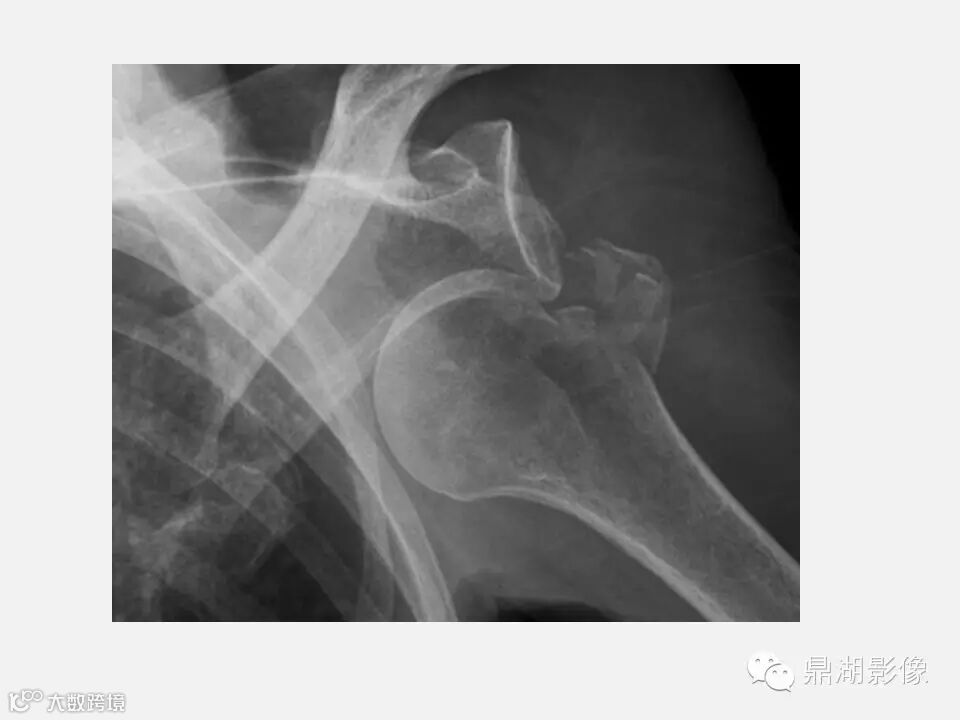

【聚沙成塔】Hill-sachs骨折知多少?